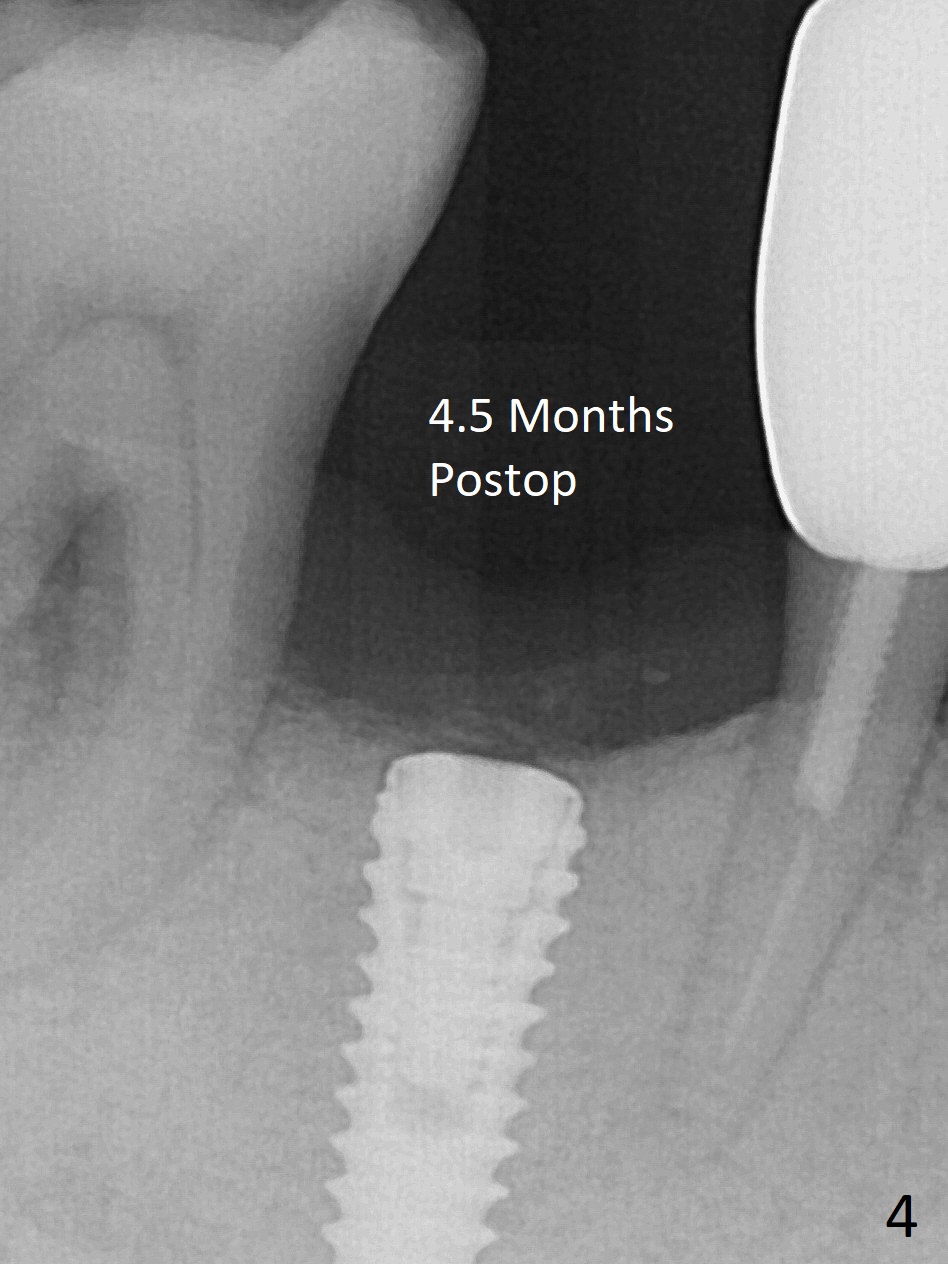

At the time of surgery, there are no 5x10 mm implants in the office for the sites of #14 and 15. Reanalysis of CT shows that there is enough bone for 11.5 mm implants. Before implant placement (Fig.1), there is no perforation of the sinus floor, as shown by probing and nasal blowing test. When a 3.5x11.5 mm implant is placed at #29 in the same appointment, it appears to be supracrestal buccal. Autogenous bone (Fig.2,3 *) is placed in the osteotomy following insertion of a healing screw (S). Periodontal dressing is applied, but it is dislodged after dinner. In fact there is bone coronal to the implant 4.5 months postop (Fig.4), which is confirmed during uncover procedure. There is no abnormality at #14 or 15 4.5 months postop (Fig.5). Impression is taken following extraction of the abnormally shifted opposing tooth #18.